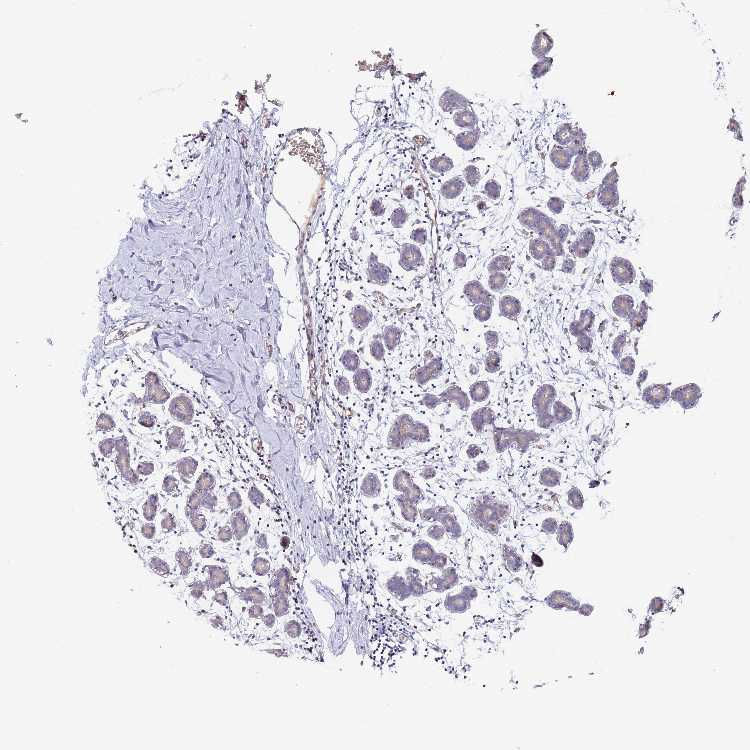

BREAST - Antibody stainingi

Antibody staining in the annotated cell types in the current human tissue is reported as not detected, low, medium, or high, based on conventional immunohistochemistry profiling in selected tissues. This score is based on the combination of the staining intensity and fraction of stained cells.

Each image is clickable and will lead to virtual microscopy that enables deeper exploration of all samples and also displays staining intensity scores, fraction scores and subcellular localization as well as patient and tissue information for each sample.

Antibody HPA045690

Adipocytes Not detected

Glandular cells Not detected

Myoepithelial cells Not detected